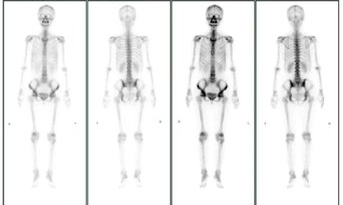

全身骨扫描未见转移

3.png